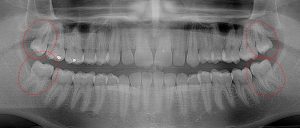

This 34 year old patient has all four third molars present (circled) and fully erupted into occlusion. They appear disease free…but are difficult to keep clean. 3rd molars are the most likely teeth to decay or have gum disease with a >98% probability that decay and gum disease will occur around all four teeth over this patient’s life time.